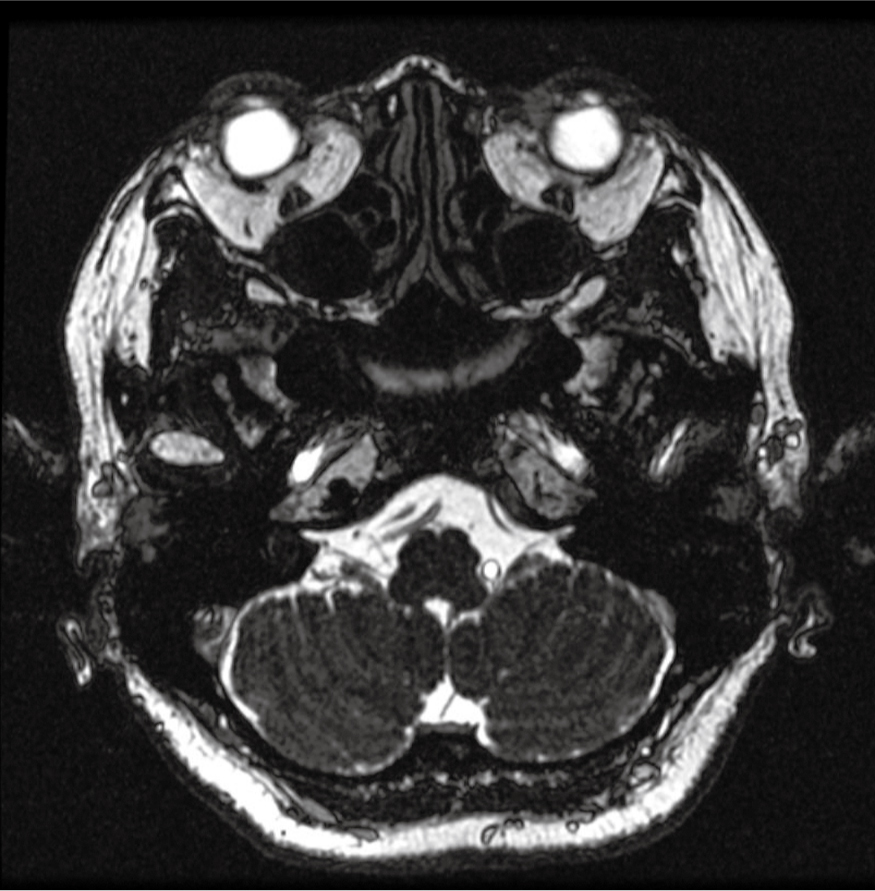

MRIT1WI画像:両側内耳道に聴神経腫瘍を認めなかった(図3)。

両側内耳道に聴神経腫瘍を認めなかった